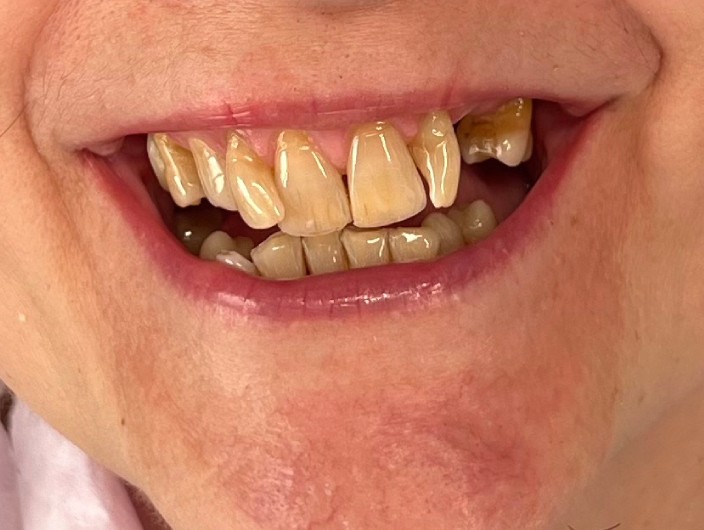

Zaprezentujemy serię poruszających historii pacjentów, którzy zdecydowali się na kompleksowe leczenie dentystyczne. Od przypadków zaawansowanej próchnicy, przez wypadki, które wymagały rekonstrukcji zębów, po pacjentów marzących o hollywoodzkim uśmiechu dzięki zastosowaniu licówek – każda historia jest dowodem na to, jak nowoczesna stomatologia może odmienić życie.

Metamorfoza uśmiechu: usunięcie przebarwień i kamienia nazębnego.